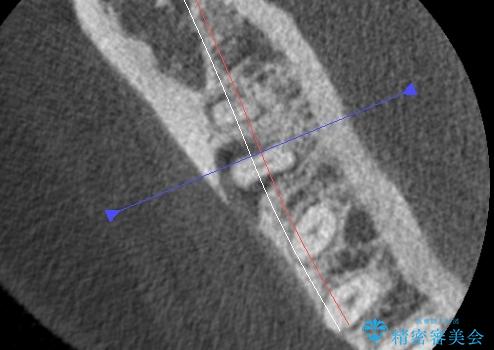

治療途中、マイクロスコープでも根管が追えないほど狭く細くなった根管へと変性しており根管の拡大形成が難しい状況でした。

CTを撮影し少しづつ丁寧に根管を探索することで無事根管再治療を行い、症状がなくなりました。